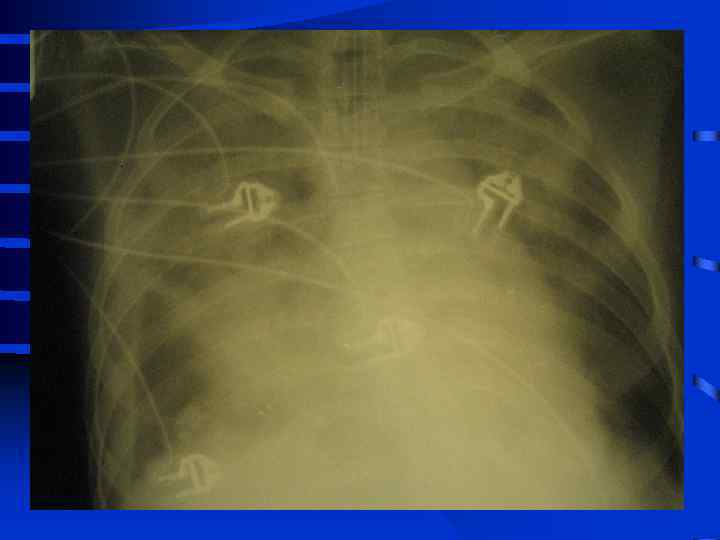

• III стадия необходима респираторная поддержка, сознание нарушено, индекс оксигенации менее 200, шунтирование 30 - 50% от величины МОК. Появляются признаки полиорганного поражения: нарушение функции кишечника (парезы, острые язвы) • и почек (эпизоды олигурии) • Рентгенографически - сливные тени, иногда первые признаки гидроторакса